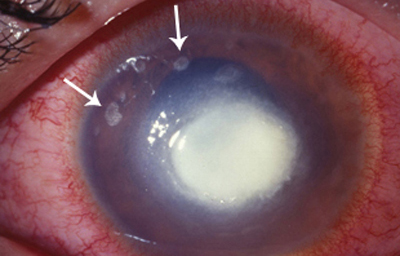

Superficie corneal irregular y grisácea, (Fig. 1, 2) con opácidades granulares en parche y formación de líneas epiteliales elevadas de aspecto granular (Fig. 3), que pueden arborizar dando imágenes de pseudodendritas. Opacidades superficiales satélites. (Figura 4) Inyección ciliar. Ulceración epitelial variante. (Figura 5).

Fig. 4 Focos satélites. Síntomas de meses evolución.